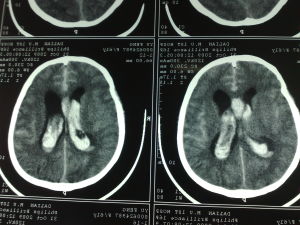

珠網膜下腔出血症狀蛛網膜下腔出血,多發生在30至40歲的年輕患者。由於一處腦動脈破裂,血 液進入包繞腦組織並充滿腦脊液的蛛網膜下腔,壓迫大腦致死,是一種危險的病症。